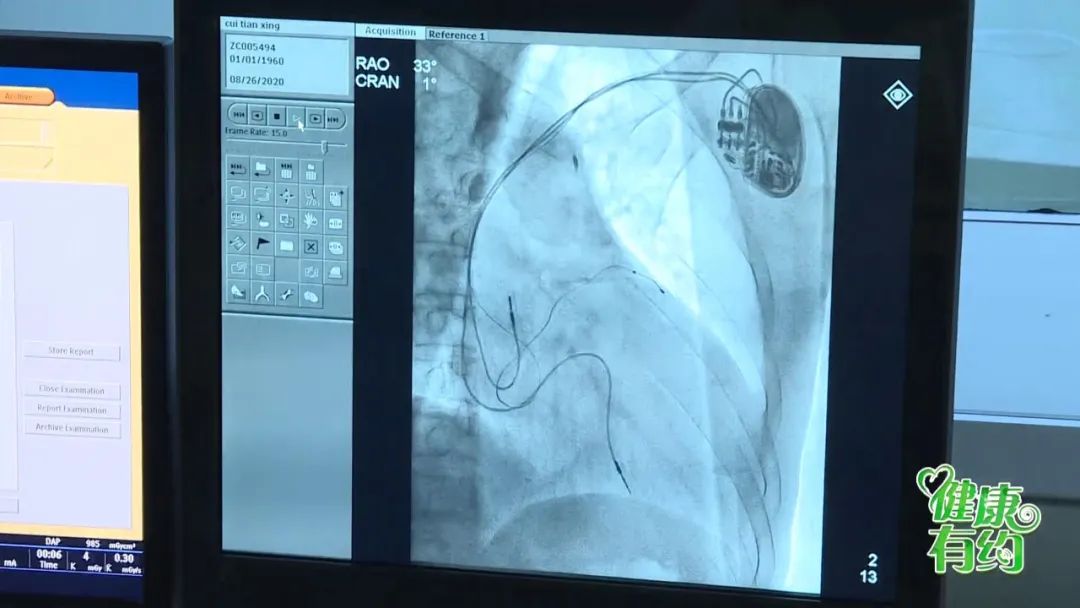

通过对杨女士完善检查,并组织专家讨论后,决定对其进行心脏的再同步化治疗。

十堰市人民医院心脏病中心开展的CRT-D心脏再同步化治疗除颤起搏器,已成为中重度慢性心衰一种重要的治疗手段,能够极大地缓解患者症状、改善生活质量,降低死亡率。

谭主任介绍,像杨女士这样严重心衰合并左束支传导阻滞的病人,就是因为负责心电传导到左心室的“电缆”被切断了。左右心室收缩不同步,心脏不能协调有效的工作。而心脏再同步化治疗除颤起搏器的植入,可以使右心房和右心室同步,左心室和右心室同步,从而增强心脏的泵血功能,明显地改善病人的生活质量。

十堰市人民医院心血管内科三病区主任 谭利国:心功能指标的正常值为50%-70%之间。术后,杨女士的指标已经从25%涨到了41%。

心脏再同步化治疗除颤起搏器,俗称三腔起搏器,其植入手术操作复杂、难度大,结合了冠状动脉介入操作技术、心脏电生理检查、治疗操作技术及起搏器操作等复杂的操作技术,且在冠状窦静脉血管内操作,因血管壁较薄弱,无肌肉层,且有静脉瓣阻挡,增大了手术操作的风险。